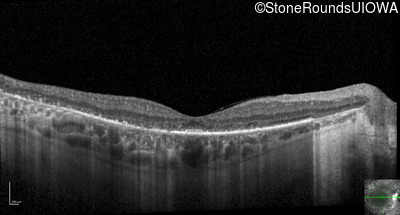

Optical Coherence Tomography - Right - 20/40 -1

Exemplar / OCT Stack

OCT Stack